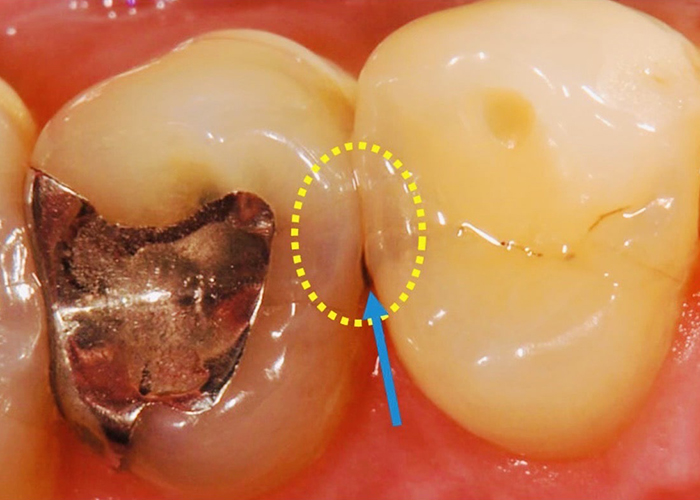

虫歯が疑われたが削らずに済んだ例

視診では歯間部が黒く透けており虫歯が疑われ治療が必要そうな状態 |

レントゲンでは虫食い状に黒く写ってはないので深く虫歯は進行してはいないと判断した |

レーザー診断にて数値が「40」だったため『初期虫歯』と判断し、削らず経過観察とした。 |

このように数値で虫歯の進行状況がわかるため、なるべく削らない治療が可能です。

当院では61以上の数値で治療が必要と判断します。

視診では歯間部が黒く透けており虫歯が疑われ治療が必要そうな状態

レントゲンでは虫食い状に黒く写ってはないので深く虫歯は進行してはいないと判断した

レーザー診断にて数値が「40」だったため『初期虫歯』と判断し、削らず経過観察とした。